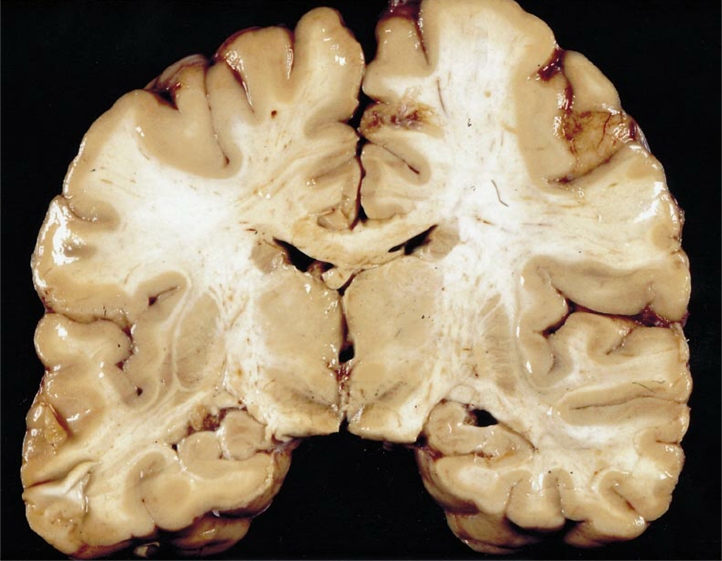

Which plane is shown here?

coronal